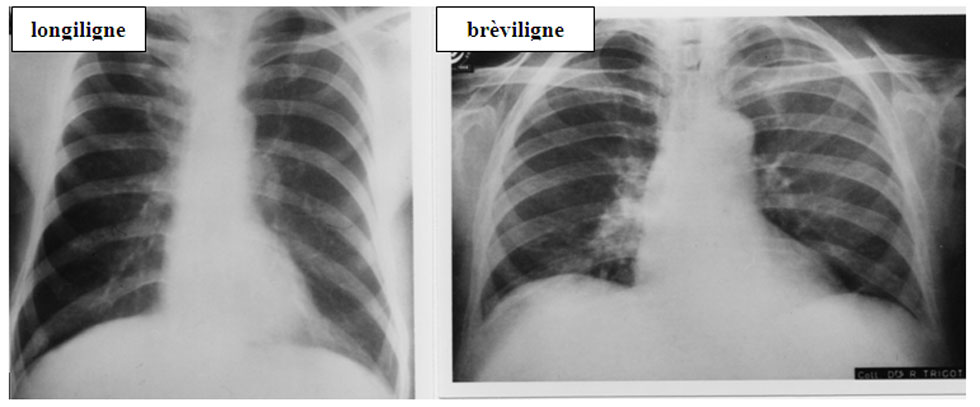

8 . 2 . 2 . 1  -  Morphotype (figure 25)

Chez le sujet bréviligne , le coeur apparaît « horizontal » c’est à dire étalé sur le diaphragme avec un pédicule vasculaire élargi. A l’inverse chez le sujet longiligne, le coeur est « vertical », allongé avec un pédicule vasculaire étroit.

Figure 25 : Morphotype